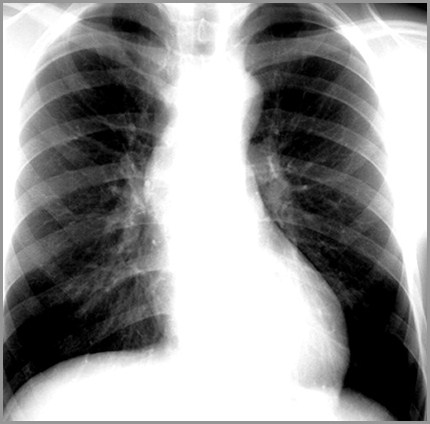

Aortic Stenosis Chest X Ray - Wikidoc

Aortic stenosis chest x ray - wikidoc wikidoc.org

ray chest aortic stenosis hypertrophy ventricular left cxr lvh calcification wikidoc hypertension failure heart bicuspid medbullets lecture radiology notes